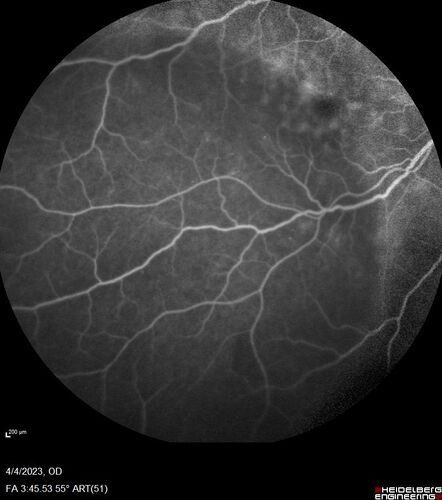

Syphilitic optic neuritis

Two weeks ago she woke up with blurred vision in the left eye.  She usually gets up at 5 AM.  Then she noticed a gray spot in the left eye that did not go away.  This is new for her.  The gray spot is not getting any better or worse in the left eye. (4/4/23)

VA OD: sc20/80 PH20/50 NscJ10

VA OS: sc2'/200 Nsc20/400

IOP: TP: OD:15 OS:16

No AC or vitreous cells - later images was with second eye involved with uveitis.  Patient received IV PCN and was lost to follow-up